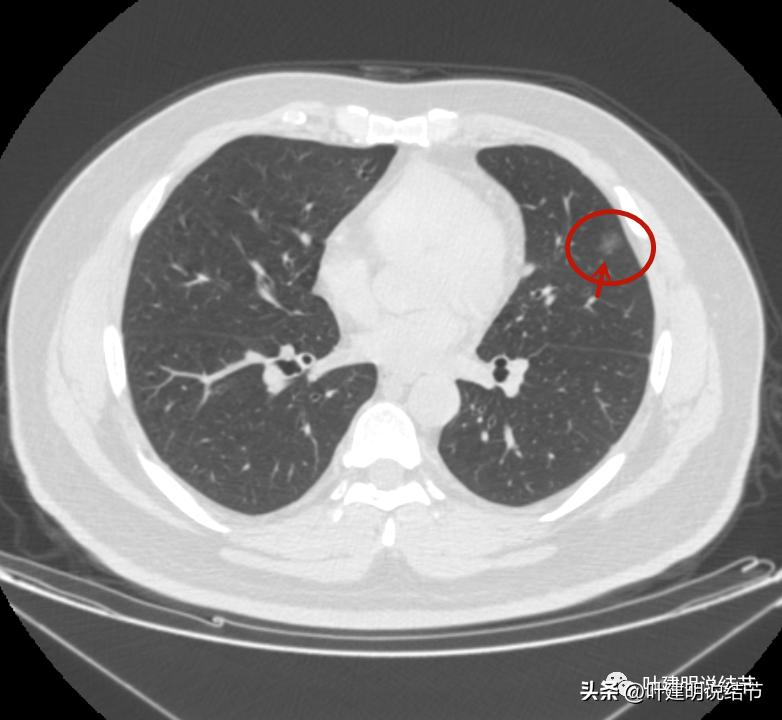

左上病灶1:磨玻璃结节,轮廓清楚伴微血管进入,中间似乎有空泡征,感觉像原位癌或不典型增生;

左上病灶2:混合磨玻璃结节,密度偏高,边缘稍糊,但轮廓相对清,有微血管分支进入,考虑微浸润性腺癌或浸润性腺癌可能大;

左上病灶3:混合磨玻璃结节偏实性,内部密度不均,整体轮廓清,有浅分叶,也有小血管关系密切,考虑浸润性腺癌可能性大;

左上病灶4:舌段磨玻璃结节,边缘显力糊,整体轮廓较清,不典型增生可能性大点。